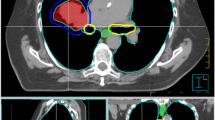

This approach requires accurate definitions of the volumes to be treated. For the tumor, these were defined as GTV, CTV, ITV, and PTV in accordance with the ICRU reports 50 and 62. For the OAR, we used terms that are analogous with those for the tumors, i. e., OAR, IRV, and PRV. We defined the OAR as the volume segmented in the planning CT, and the IRV as the volume derived from 4D-CT. Describing the relation of PTV and the PRV to each other (Fig. 1), we defined the nomenclature of volumes in set theory notation to be 1) PTV for the total PTV, 2) the simultaneous protection volume (PTVSIP) for the intersection of the PTV and the PRV, PTVSIP = PTV ∩ PRV, and 3) the PTV without intersection with the PRV as the dominant PTV, PTVdom = PTV\PTVSIP. The term dominant was chosen to imply that the SIP approach is only valid for small volumes of PTVSIP.

Contouring and planning using the simultaneous integrated protection (SIP) concept. Scheme of a critical organ at risk (OAR; blue, left side) with its planning risk volume (PRV) overlapping with the planning target volume (PTV, pink). The dominant PTV (PTVdom = PTV\PRV; orange) is the prescribed dose in the conventional way, whereas the PTVSIP (=PTV ∩ PRV; purple) is prescribed a lower dose to stay within the dose constraints for the OAR